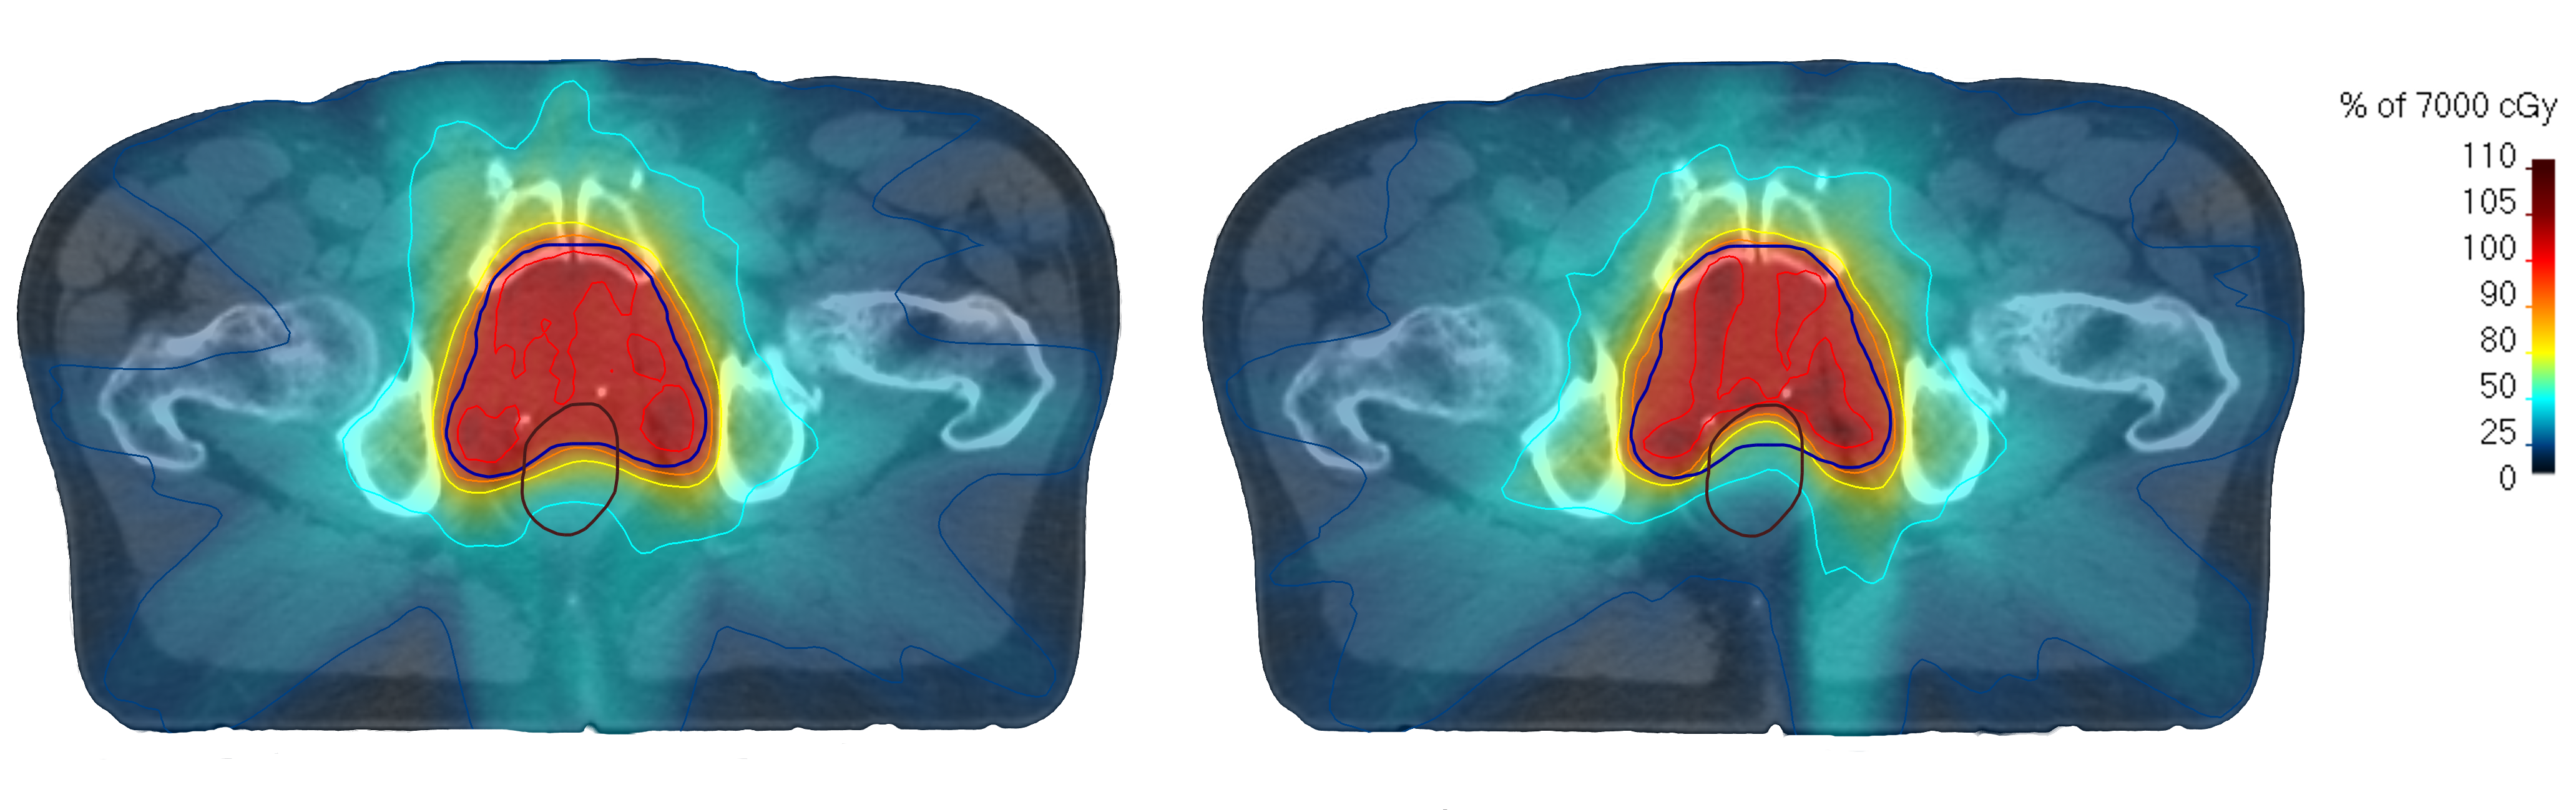

Finally, to demonstrate that the proposed dose mimicking method can successfully utilize the predictive distributions outputted by the MDN, we create two deliverable plans for a patient in the holdout set mimicking, respectively, μ1subscript𝜇1\mu_{1} and μ2subscript𝜇2\mu_{2}. Spatial dose and DVH comparisons are shown in figures 10 and 11. For both cases, one can see that the spatial dose distributions follow the respective predictive modes well, although being slightly less conformal. This is most likely due to the predictions being overly optimistic in the rate by which dose falls off around the target area. One can also see that the DVHs of the mimicked plans followed closely or were in some cases even better than those predicted. While these results show the merits of a probabilistic dose mimicking method, in a clinical setting, one would likely need to further post-process the obtained plans before approval and delivery.

Refer to caption

Figure 10: Comparison of predicted and mimicked spatial dose distributions in a transversal slice for the cases of mimicking μ1subscript𝜇1\mu_{1} and μ2subscript𝜇2\mu_{2}, respectively.